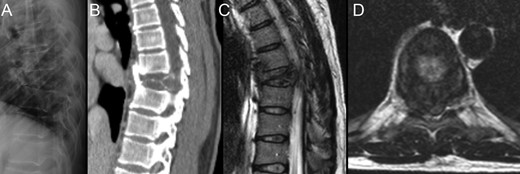

The radiographic study identified an expansive lesion in the eighth thoracic vertebra (T8), with local kyphosis and imminent instability. She performed a computed tomography (CT) scan and magnetic resonance imaging (MRI), which better defined the bone involvement and already revealed invasion of the medullary canal (Fig. 1). A percutaneous CT-guided core-needle biopsy was then undertaken, and the histologic report confirmed the diagnosis of giant-cell tumor.

Preoperative imagiologic study; involvement of T8 by the giant-cell tumor as presented in plain radiograph (A), CT scan (B) and MRI (C and D). Notice the tumor mass protruding into the vertebral canal.